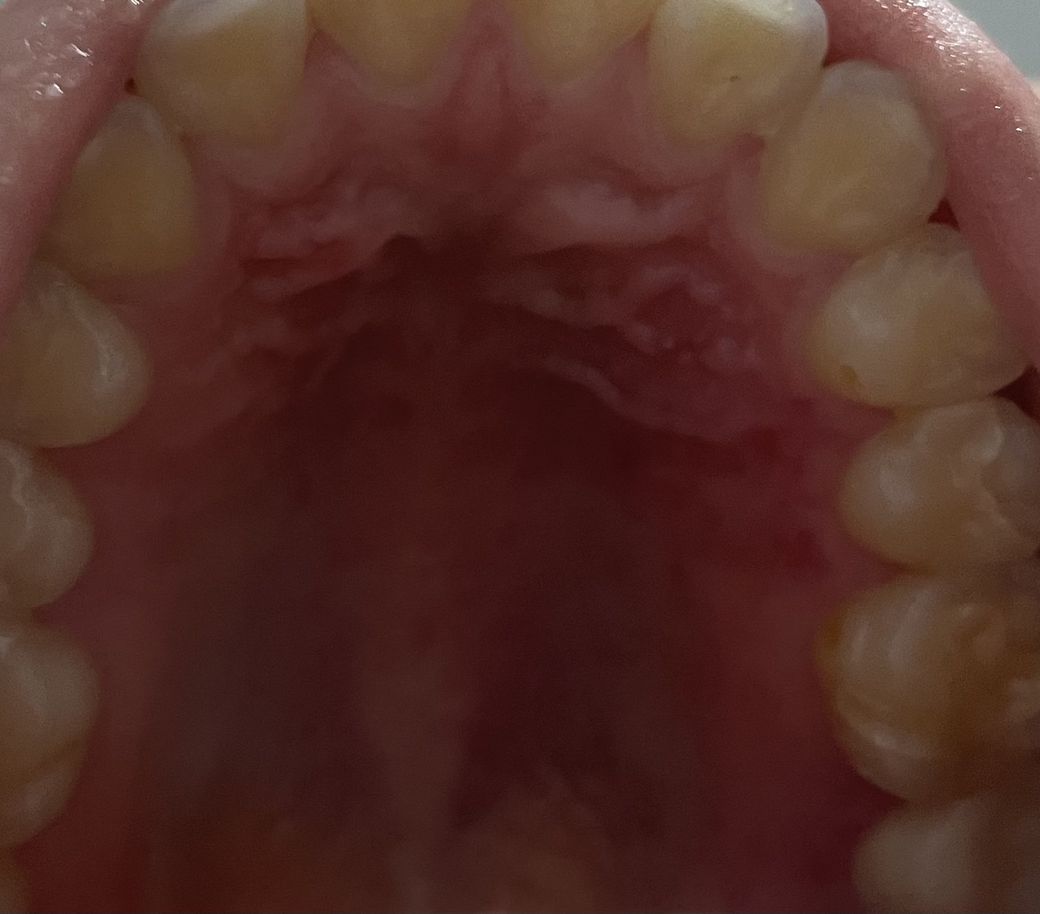

입천상 염증인가요? (사진첨부)

경구개(?) 쪽이 붓고 통증이 있습니다 .

밥먹을 때마다 아파요ㅠㅠㅠㅠ 병원 가봐야하나요??

아니면 시간 지나면 자연히 낫나요??ㅠㅠㅜ

내일 교정기 끼러가는데 문제 없을까요... ?!

입천장쪽 잇몸이 붓고 통증이 있어서 불편하시군요.

입천장쪽 잇몸은 음식물에 의한 외상이나 찔림 등에 의해 붓고 염증이 생길 수 있지만 수일 내에 회복되어 괜찮아집니다.

사진만 봐서는 크게 이상이 있어보이거나 부은 것 같지는 않네요. 통증이 있다면 약국에서 진통제를 복용하시면서 괜찮아지기 기다려볼 수 있습니다.

사진을 통해 보았을 때에는 특별한 이상 소견이 의심되는 것은 없습니다. 다만 직접 검진을 받는 것보다 정확하지 않으니 만큼 치과에 방문하시어 이상이 있는지 여부는 재차 검진 받아보시길 권고드립니다.

튀김류 음식을 드시거나 뜨거운 음식을 드셔서 까진것처럼 보입니다.

eryhemaplakia인 적반증일 가능성이 있습니다. 일시적으로 나타났다면 문제가 되지 않지만 2주 안에 사라지지 않는다면 반드시 치과 방문 후 검사를 진행하는 것이 좋습니다. 캔디다균에 의한 감염일 가능성도 있으며 특별히 입천장에 자극이 없는데 지속적으로 나타난다면 조직검사가 필요합니다.

해당 부위가 평소에 비해 붓는 원인은 여러가지가 있으며, 부위가 입 안쪽이므로 교정장치를 부착하는 데는 큰 문제는 없을 것으로 보이나 교정장치 부착 전에 해당 부위에 대한 정확한 검사를 받는 것이 좋을 것으로 보입니다.

해당 사진상에서는 미약하게 발적이 있어보이지만 해상도가 낮아서 정확한 진단은 힘듭니다.

사진상에서 뚜렷하게 문제가 있는 상황으로 보이지는 않으나 가까운 치과에 내원하셔서 검사를 받아보시길 권합니다.

사진의 주름진곳은 루게 라는 곳으로, 원래 정상적으로 주름이 있는곳입니다.

부종이 있는것같고 통증이 있다면 치과에서 진료를 받아보시기 바랍니다. 감사합니다.